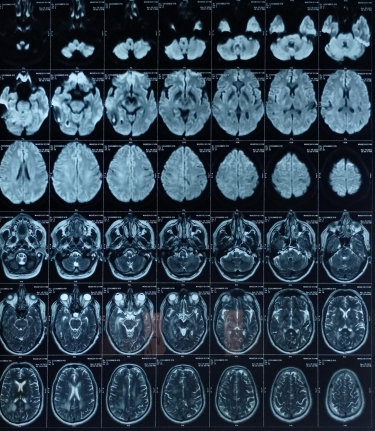

Early-onset dementia (onset before age 65) is a thought-provoking ailment with many possible causes, including early-onset familial Alzheimer’s disease, frontotemporal lobar degeneration, Parkinson’s dementia, Lewy body dementia, disorders of amino acid and organic acid metabolism, leukodystrophies, lysosomal storage diseases, disorders of metal metabolism, and mitochondrial diseases [6]. In our patient, the history, physical examination, laboratory investigations, and neuroimaging were not suggestive of these causes and prompted the search for a rare etiology. The most common MRI finding associated with CADASIL is basal ganglia and white matter hyperintensities in T2-weighted sequences that start as punctate or nodular foci and then often become confluent, extensive, and usually symmetrical, mainly in the periventricular region, anterior temporal pole, external capsule, the centrum semiovale, and frontal and parietal areas. In our patient, diagnosis was made mainly from MRI findings as seen in fig. 1, 2.

Fig. 2: Extensive hyperintensity on T2W/FLAIR sequence is seen in bilateral thalamus and basal ganglia, both cerebellar hemisphere, mid brain, pons and in deep white matter of both cerebral hemispheres